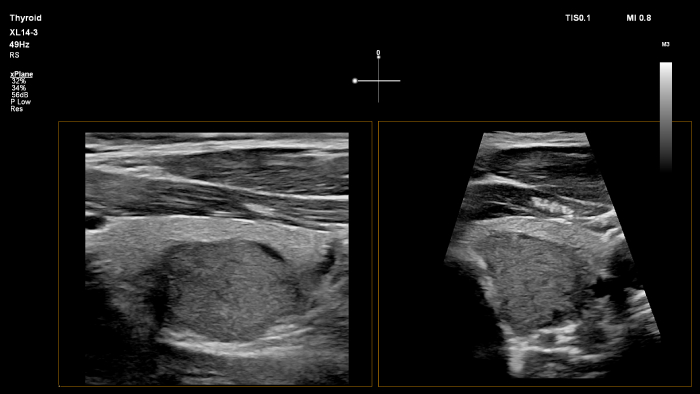

O transdutor PureWave eL18-4 da Philips inclui matrizes de cristais multilinhas que proporcionam imagens de corte fino para uma excecional resolução dos detalhes, ao mesmo tempo que fornece imagens e penetração extraordinárias.